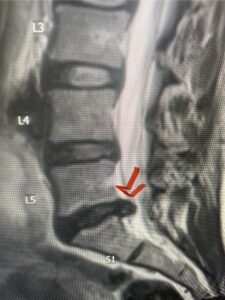

In this next case, this patient is a 47 year-old female who presents with intractable low back pain with severe pain, numbness, and weakness in the right lower extremity that had gotten progressively worse over a year. The patient had failed conservative management including physical therapy and epidurals. She was noted to have ⅘ weakness of plantar flexion. MRI demonstrated a large right L5-S1 disc herniation with severe compression of the descending right S1 nerve root (Fig 3). It was decided to perform a right L5-S1 hemilaminectomy for removal of the disc fragment and decompress the S1 nerve root. When you expose the disc, one must be certain to release any anterior adhesions to the nerve root in order to prevent a dural tear during retraction of the nerve root. It is also important to make sure during exposure and you finally encounter the dura after removing the ligamentum and fat, to make sure you are looking at the nerve root and not the main trunk of the thecal sac because if you don’t you can avulse or damage the nerve root if you retract the wrong structure.

Fig. 3a: Sagittal and axial T2-weighted lumbar MRI images demonstrating large right L5-S1 disc herniation (red arrows)